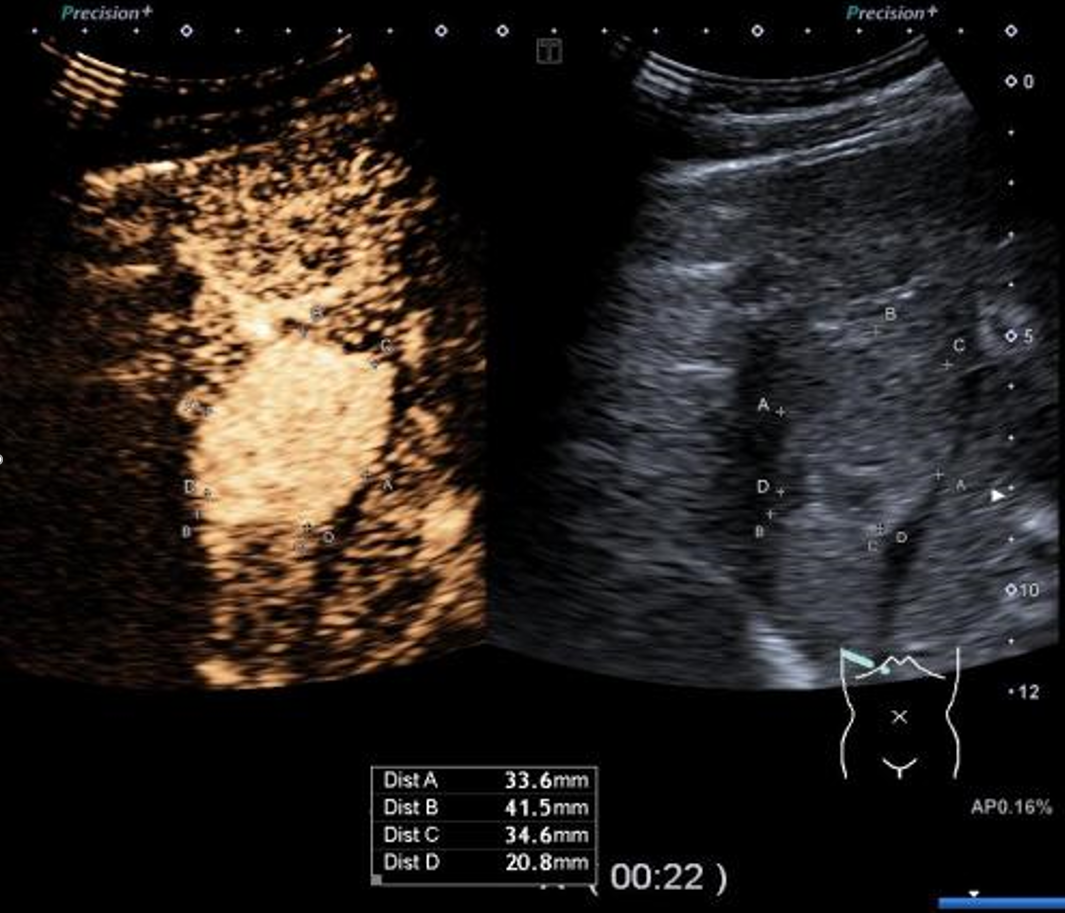

▲患者术前超声造影显示富血供

患者在手术室行纳米刀肿瘤消融术,术者在超声引导下经皮穿刺布针,共进3根针,确保电极区域包裹肿瘤,布针间距尽量要求均匀,麻醉医生为患者注射肌松药物,随后开始消融。术中根据电流反馈多次测试调整消融参数完成消融,消融过程中电流上升反馈良好,无不良反应。术中结合腔镜辅助下的超声探查后,又发现了除术前磁共振提示的两枚小病灶外额外共计4枚肝脏微小病灶,术中超声造影评估考虑小肝癌。